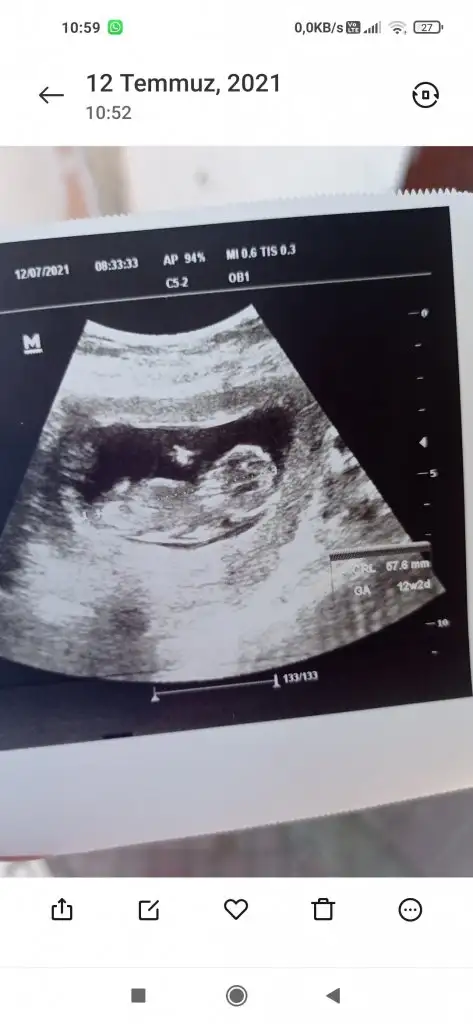

Kız görünüyor11+3 e göre tahmininiz nedir?

Net kız mı yoksa büyük ihtimal mi? Teşekkür ederimKız görünüyor

Kız gibi geldi bana ele alıp iyice bakmıyor bakıyorum tahminimi söylüyorum üsten almış Dr belkide yanıldım başka USG varsa paylaşınNet kız mı yoksa büyük ihtimal mi? Teşekkür ederim![]()

Değişme ihtimali var mı peki? Yoksa kesin mi? 11+3 çıktı ama 12+0AA evet rengi net olunca çıkıntısı var![]()

Allah bilir canım erkek görünüyorDeğişme ihtimali var mı peki? Yoksa kesin mi? 11+3 çıktı ama 12+0

Çok erken en iyi 11 12 13 haftalar olmalı şimdilik kız yönünde ama yanıltabilir

Kız görünüyor